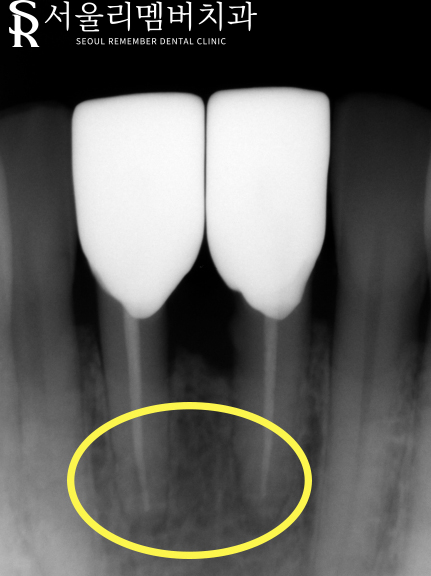

치아를 더 자세히 볼 수 있는 치근단 사진을 찍어

앞니의 상태를 정확히 파악해 보았습니다.

사진상으로 치아 안에 검정색 빈 공간으로 보이는 곳이

치아의 신경이 있는 곳입니다.

치아의 머리 부분에서 시작한 충치가

신경 쪽으로 퍼져 있는 것을 볼 수 있습니다.

아무래도 신경치료가 필요하겠다는 판단이 들었습니다.